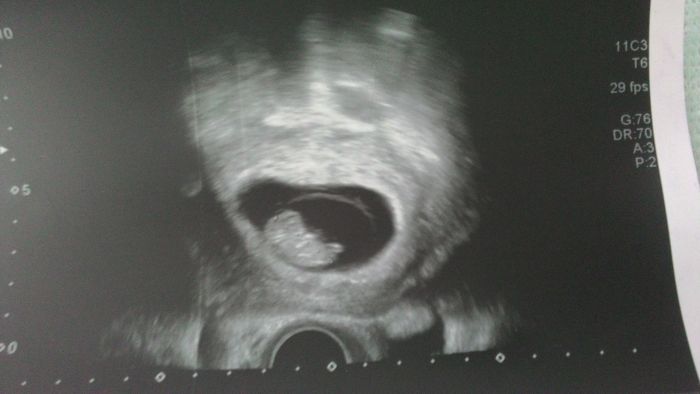

Holky, ještě přidávám fotečku našeho Haribo medvídka.:)

Moc na vás tady všechny myslím a držím palečky! Opatrujte se!

[1006326] To je krásnný...

[1006326] Činčo, to je opravdu jak gumový medvídek Haribo:-)krásný:-)a necháš si říct pohlaví?